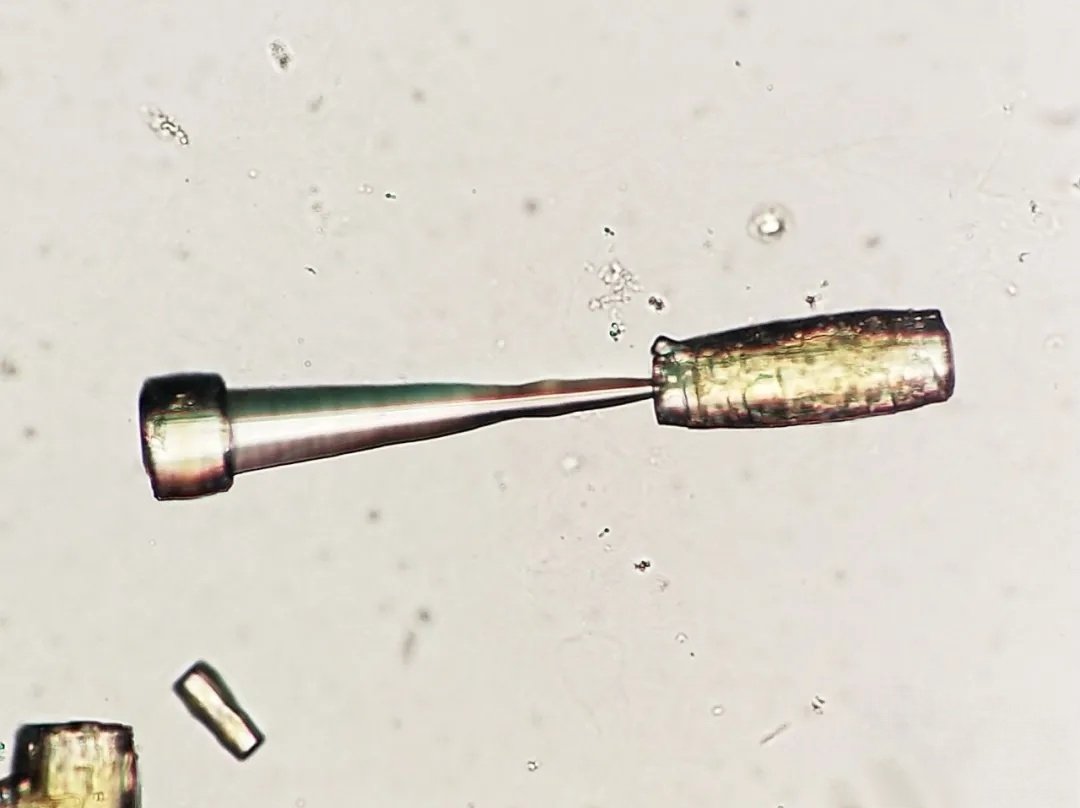

⁉️#GUpath #PEDIpath⚠️ 15YOB with a 7 mm intra testicular nodule... 🔪GROSS🔪 Woo Cheal Cho, MD GU Pathology Society (GUPS) Dr.Gauri Vidolkar MD Frank Ingram, MD Ankur Sangoi @evacomperat Daniel Skipper @AkgulMd Jonathan Zuckerman MD PhD Carla Ellis MD, MS Erasistrate Farshid Siadat, MD, FRCPC Francesca Khani, MD Peter Sadow, MD, PhD Ashish M. Kamat, MD, MBBS Nature Reviews Urology ⏭

It is unknown time! What is your guess? Make sure to follow Willy Kemp for more teaching treasures!